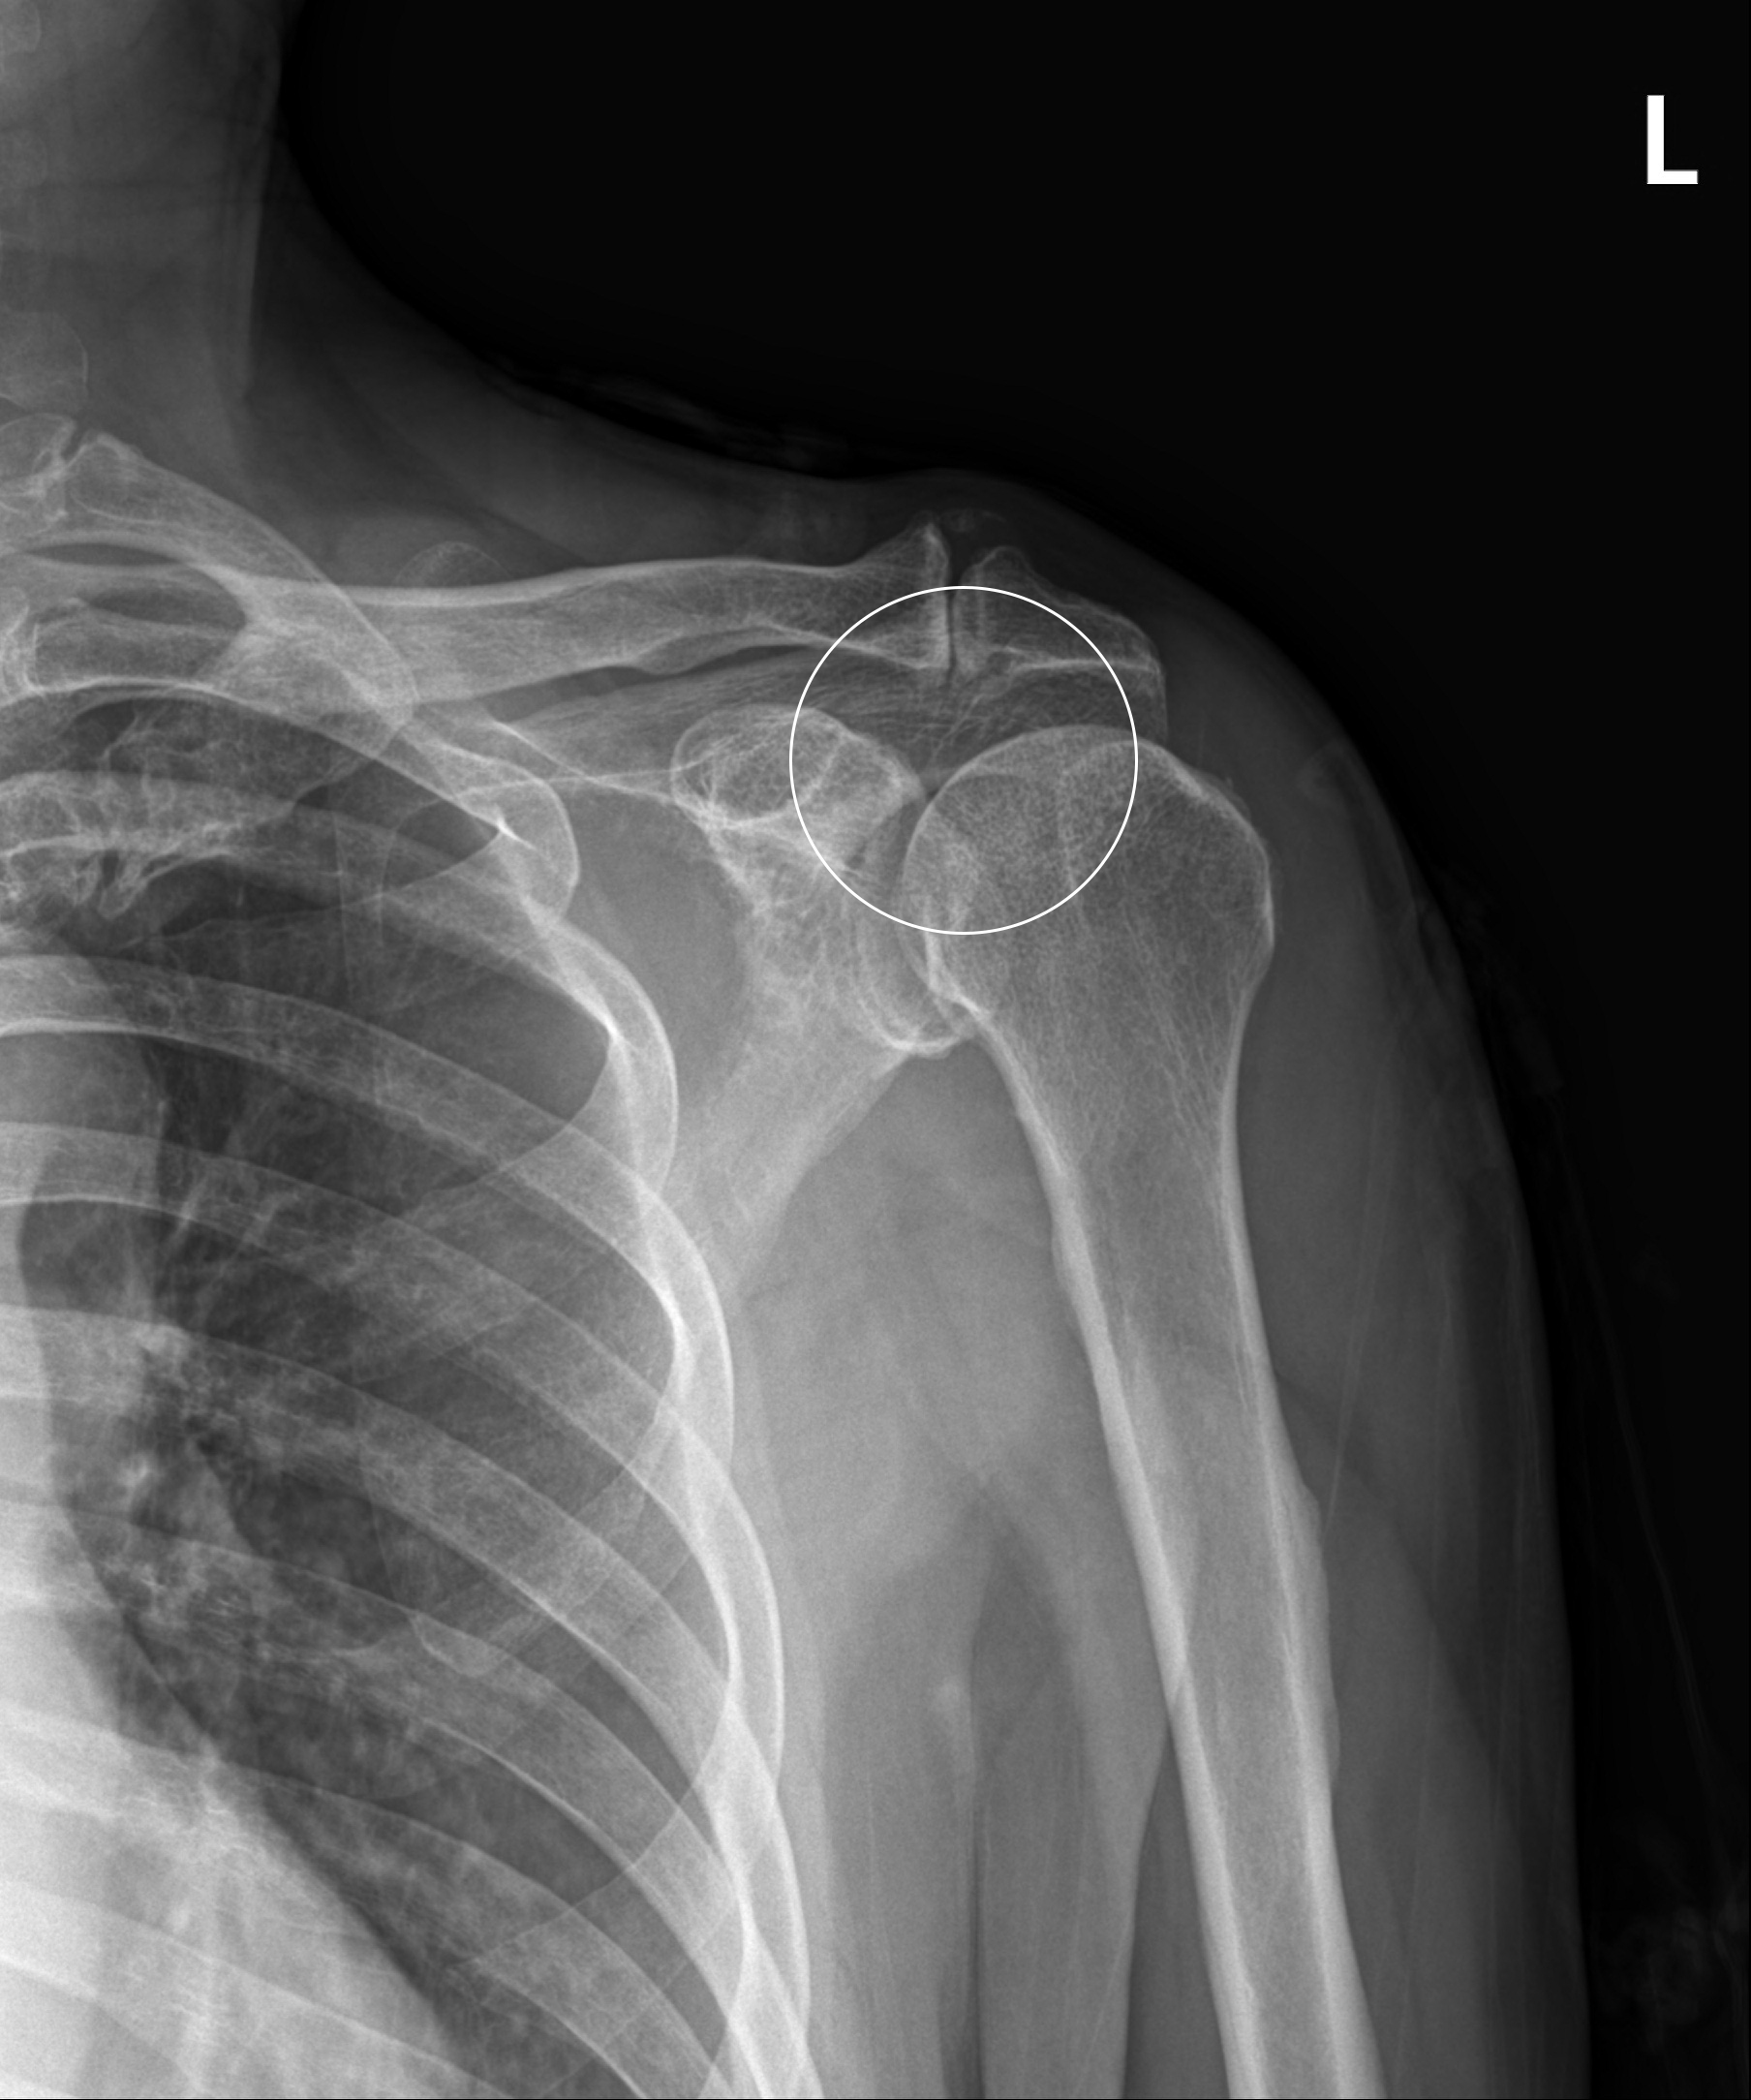

어깨충돌증후군

어깨 견봉과 위팔뼈인 대결절부 사이의 공간이 좁아지면서 뼈와 힘줄 사이에 마찰이 발생하는 질환을 말합니다. 정상 어깨관절에서는 이 공간이 충분하나 어깨를 많이 사용하거나 운동을 무리하게 한 경우 또는 퇴행성 변화 및 뼈의 변형으로 인해 견봉과 어깨 힘줄 사이에 간격이 줄어들어 마찰이 발생하고 힘줄 변성 및 통증이 발생하게 됩니다.

관절내시경을 이용한

견봉성형술 및 회전근개 변연절제술

2023-03-06

ㆍ환자 동의를 받은 자료이며, 이미지 사진은 실물과 다를 수 있습니다.